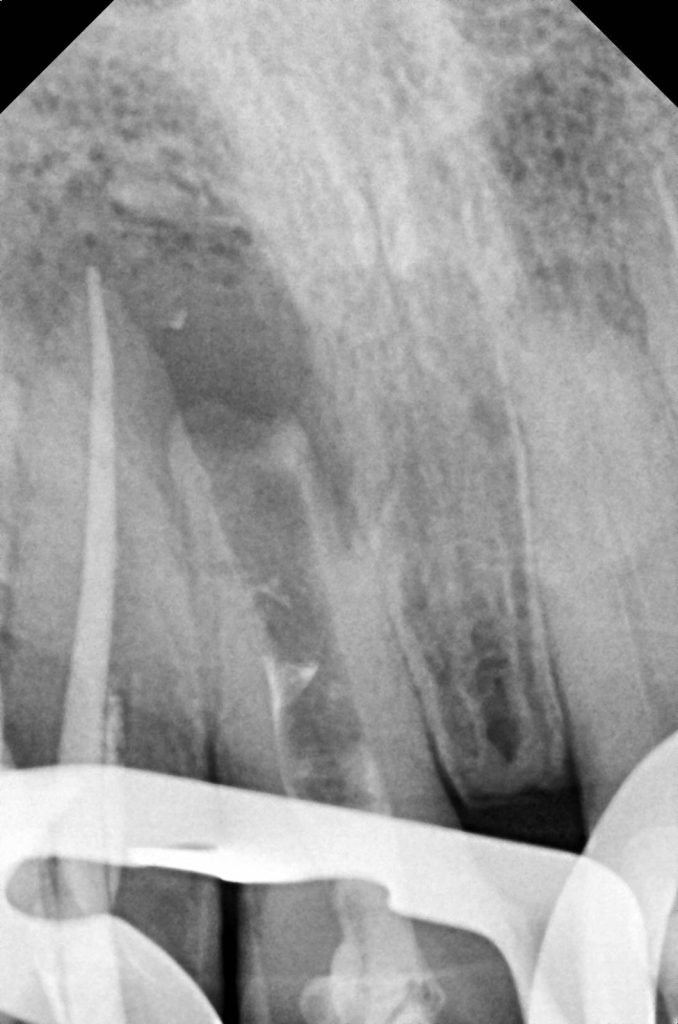

- Prior root canal therapy with open apex—managed using MTA-based apexification.

- Post-traumatic discoloration due to pulpal necrosis.

- Residual esthetic defect after apexification.

Previous MTA apexification provided apical stability, allowing safe buildup and crown retention. Non-vital bleaching minimized aggressive preparation and preserved tooth structure.